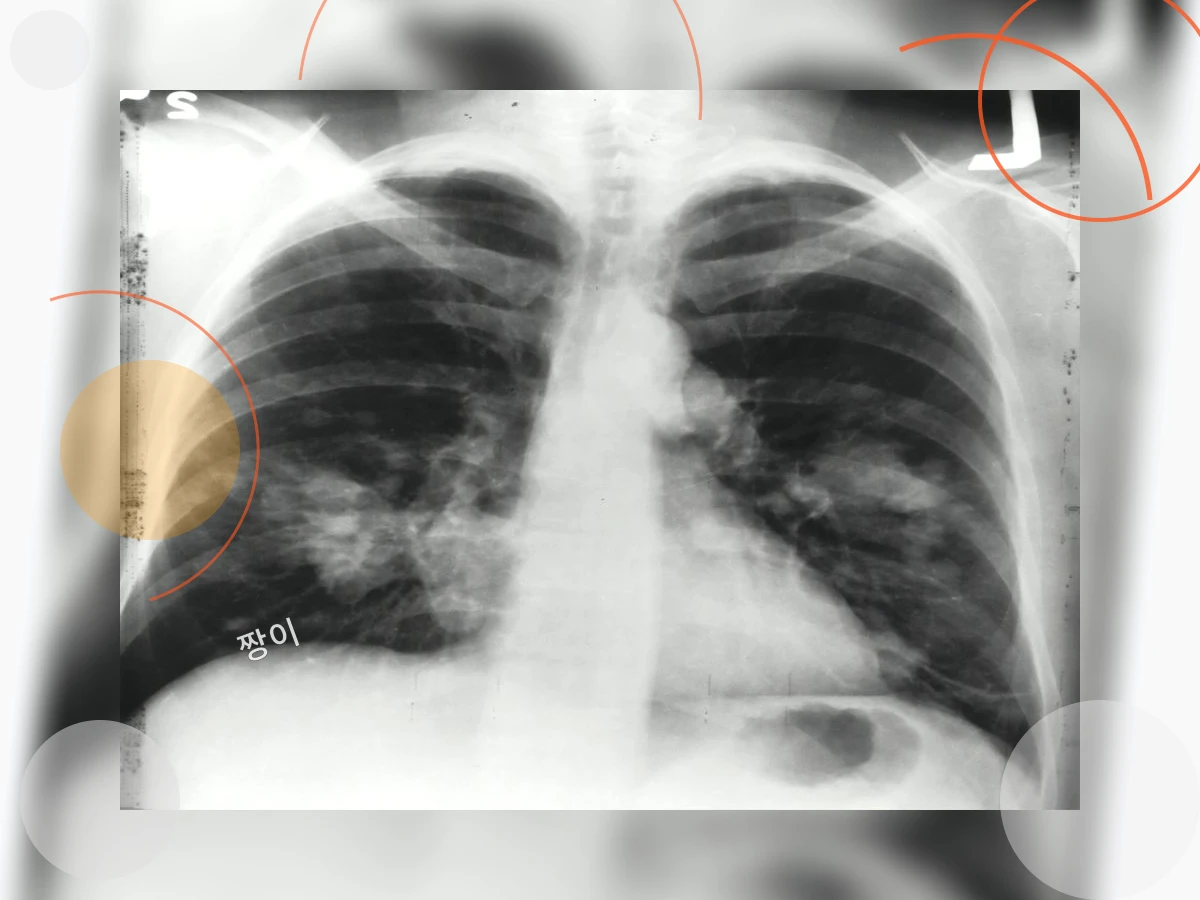

예를 들어, 감기에 걸린 후에도 기침이 2주 이상 지속된다면 기관지염을 의심해 볼 수 있습니다. 또한, 흡연자라면 만성 폐쇄성 폐질환(COPD)의 가능성을 배제할 수 없습니다. 알레르기성 비염이나 천식이 있는 경우에도 기침과 가래가 잦을 수 있으며, 심지어 역류성 식도염 때문에 기침이 유발되는 경우도 있습니다.

기침과 가래를 방치하면 만성 기관지염, 폐렴, 기관지 확장증 등 심각한 호흡기 질환으로 이어질 수 있습니다. 또한, 수면 부족, 만성 피로, 사회생활의 어려움 등 삶의 질을 크게 저하시킬 수 있습니다. 조기에 적절한 치료와 관리를 통해 건강한 삶을 유지하는 것이 중요합니다.

특히 고령자나 만성 질환자는 기침과 가래를 가볍게 넘기지 말고, 반드시 전문의와 상담하여 적절한 치료를 받아야 합니다.